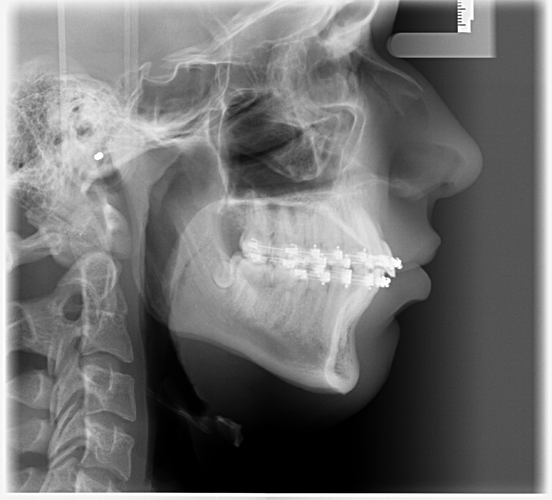

These are my CTs, how big do yall think i will ascend?

Before and after:

• Fabian_Noah_Luca_14012026_151449.png

Fabian_Noah_Luca_14012026_151449.png

2.5 MB · Views: 0